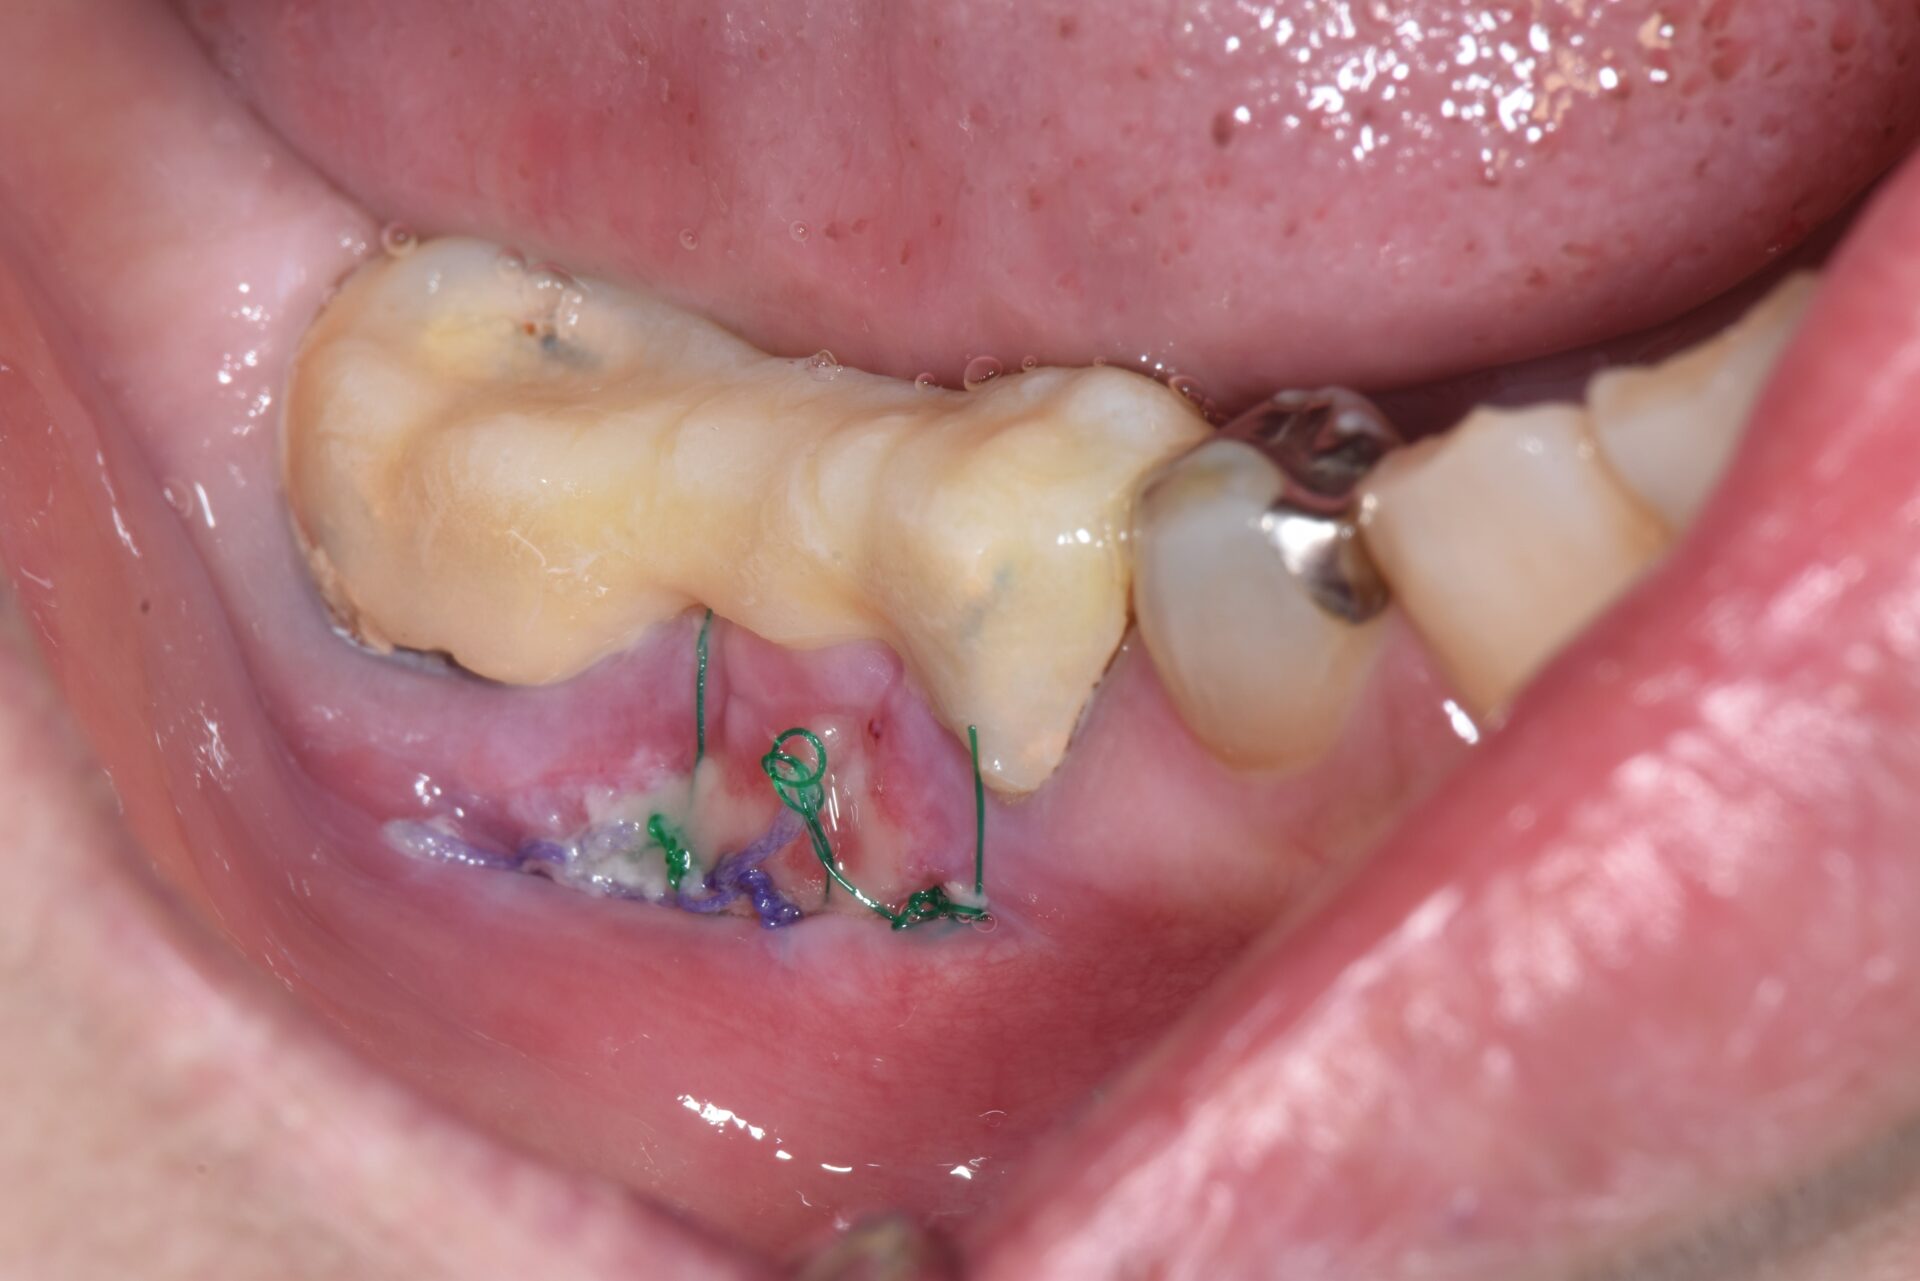

FGG(遊離歯肉移植術) 臨床例①

患者さんは、左下奥歯の周囲に付着歯肉が不足しており、ブラッシングの際に痛みがあり清掃が難しく、炎症を繰り返していました。歯肉が薄く柔らかいため、長期的な安定には不安があり、遊離歯肉移植術(FGG) を行うこととしました。

3か月後、角化歯肉がしっかりと定着し、清掃性の向上と炎症の改善を確認。歯周組織の環境が強化され、将来の歯の喪失リスクを低減することができた。

術前

術後1ヶ月

術後3ヶ月